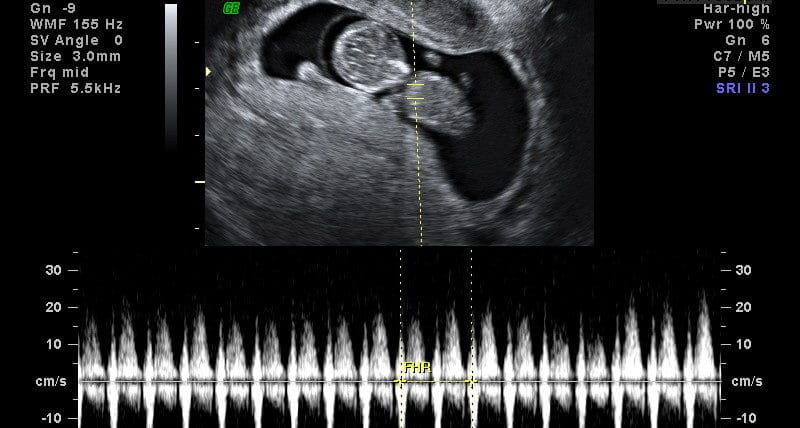

Com cerca de 5 semanas de gestação, o coração do seu bebê começa a bater. Nesta fase, a frequência cardíaca fetal é um pouco maior que a da mãe: cerca de 100 batimentos por minuto (BPM). A partir deste ponto, a frequência vai aumentar cerca de 3 batimentos por minuto por dia durante esse primeiro mês. Isto é tão preciso que o seu médico poderia usar a freqüência cardíaca para ajudar a determinar a idade gestacional do seu bebê.

Até o início da 9ª semana de gravidez, a frequência cardíaca fetal normal é uma média de 175 BPM. Neste ponto, começa uma rápida desaceleração da freqüência cardíaca fetal passando para cerca de 110-160 BPM na metade da gestação. Há também uma lenta desaceleração da frequência cardíaca fetal nas últimas dez semanas de gravidez. É importante salientar que a frequência cardíaca de um bebê normal irá variar naturalmente, assim como sua freqüência cardíaca faz. Dormir, movimento e outras atividades podem causar uma variação normal um pouco acima ou um pouco abaixo da frequência esperada. Oriente-se com o seu médico.